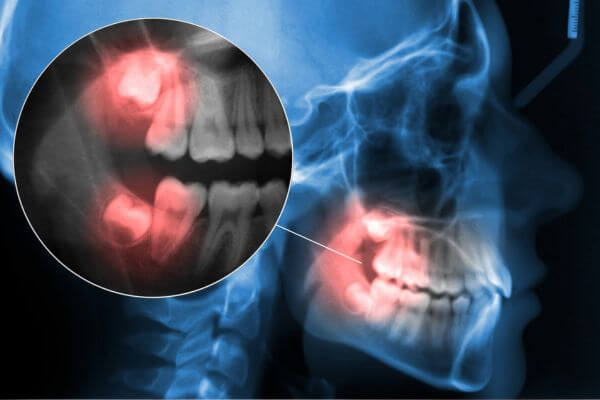

1. 3D digital diagnostics and planning

Before placing the implant, we carry out a complete study using digital radiography or 3D tomography. This allows us to plan the exact position and ensure perfect integration into the bone.